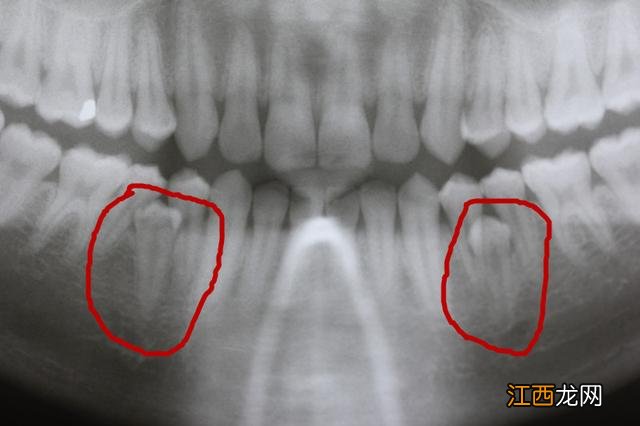

牙乳牙 有的多生牙先于所在部位恒牙的萌出,故而影响了恒牙的正常萌出和排列,患儿的家长误以为是恒牙萌出,并没有引起重视,待发现时已经错过最佳矫正的治疗时机,拔除多生牙后再配合牙齿矫正才可将牙齿排齐;也有的多生牙和恒牙同时萌出,造成恒牙萌出位置偏斜、牙列拥挤等问题;个别多生牙由于埋伏位置过深或倒置,无法萌出,不易被察觉 。(图4)

牙 无法萌出的多生上颚牙又分两类六岁 。一类是可以和我们“和平共处”,大家相安无事;另一类是由于某些原因导致多生牙发生移动,造成附近牙齿的损伤或者其继发囊肿,造成周围组织的破坏,对于这类一定要进行处理牙,否则破坏会继续增大 。(图5)